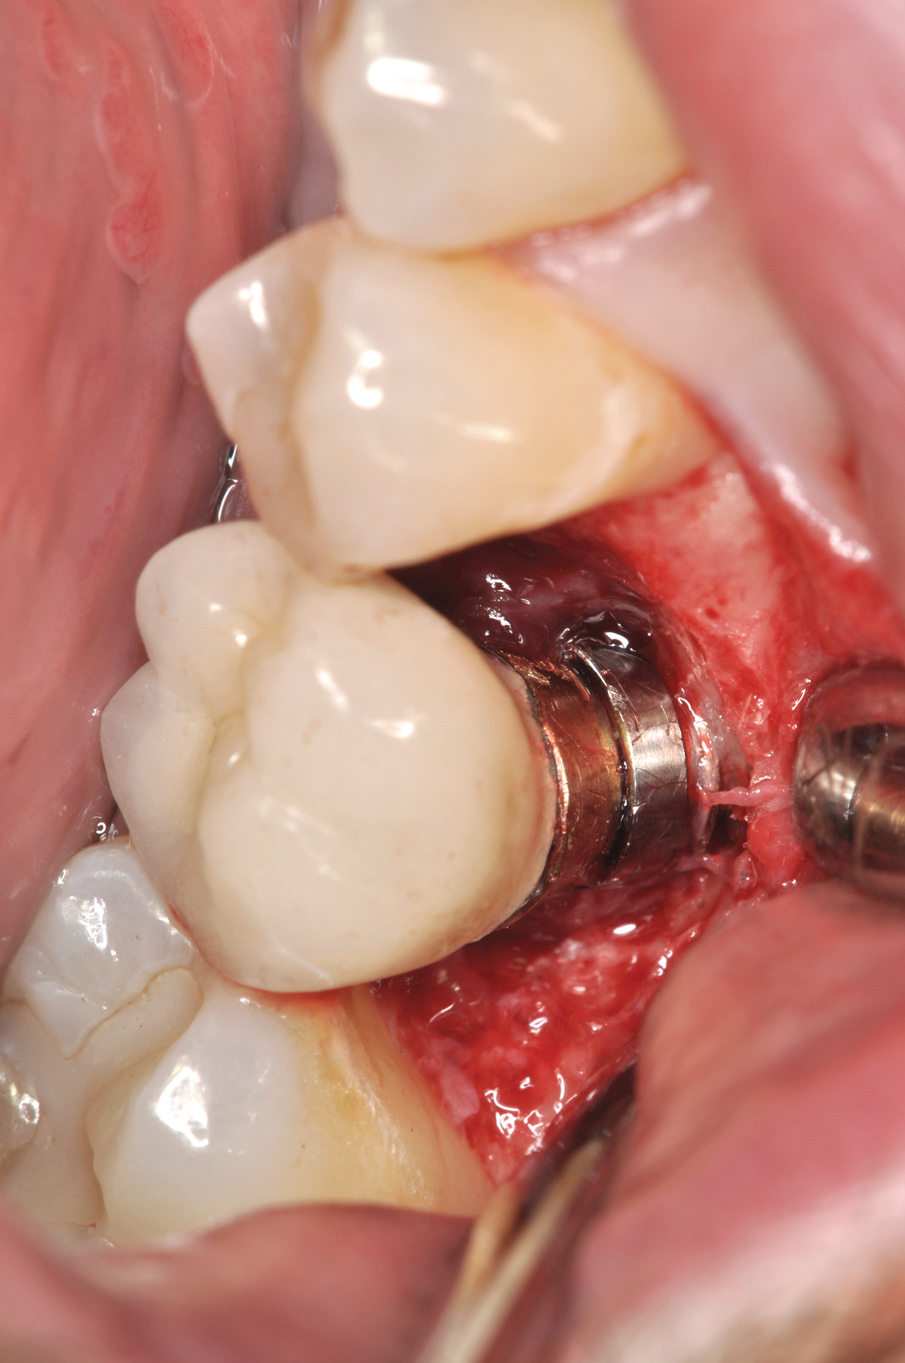

Fig 8. Loss of restoration and subsequent tissue overgrowth from broken abutment screw as shown in the radiograph (Fig 9).

Figure 8

Fig 9. Radiograph depicting fractured screw inside of the implant.

Figure 9

Fractured screws are challenging to retrieve, particularly when they are abutment screws. If the screw head is accessible, a hemostat can be used to remove it. However, when the screw breaks inside the implant (Figure 8 and Figure 9), removal can be highly complicated in order not to damage the implant’s internal threads. Therefore, many implant manufacturers have developed screw-retrieval kits. Because it is critical to be able to visualize the area, magnification using loupes and a surgical microscope may be necessary.8 Additional methods can be used to remove the fractured screw. A ¼ round bur set on a high speed can be used by lightly activating it, touching only the side of the screw. After repeating this technique several times, the screw may be able to be backed out with an explorer tip. Ultrasonic tips with copious irrigation may also dislodge the screw.7,20 In cases in which this fails, a small slot can be made in the head of the screw to back it out.21 If screw threads have been damaged during retrieval, they may be retapped using a tool obtained only from the implant manufacturer.7